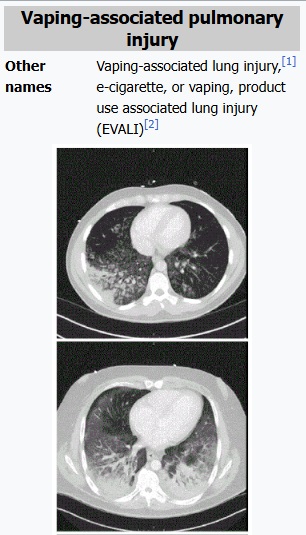

การระบาดของโรค EVALI จากบุหรี่ไฟฟ้า

ปี 2020 ศูนย์ควบคุมและป้องกันโรคแห่งชาติสหรัฐอเมริกา (CDC) รายงานพบผู้ป่วยโรคปอดจากการใช้บุหรี่ไฟฟ้า (E-cigarette or Vaping use-Associated Lung Injury : EVALI) จำนวน 2,807 เคสในสหรัฐฯ และมีผู้เสียชีวิตจากโรค EVALI ในขณะนั้นจำนวน 68 ราย

ผลการตรวจสอบของเหลวจากปอดของผู้ป่วย EVALI พบทั้งสาร THC หรือสารสร้างความมึนเมาที่อยู่ในกัญชา และ วิตามินอี ที่ใช้เป็นสารเพิ่มความข้นในน้ำยาบุหรี่ไฟฟ้า ซึ่งหากสูดดมก็จะส่งผลเสียต่อระบบทางเดินหายใจ

คาดว่าส่วนผสมของสาร THC และวิตามินอี น่าจะมาจากบุหรี่ไฟฟ้าที่มีการดัดแปลงส่วนผสมหรือบุหรี่ไฟฟ้าที่ลักลอบจำหน่ายในตลาดมืด เป็นการเพิ่มอันตรายจากการสูบบุหรี่ไฟฟ้ายิ่งขึ้น